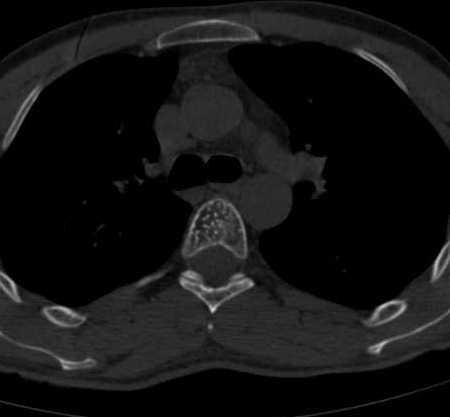

4.1 Radiografía / TC

- Vértebra: trabeculación vertical (“corduroy” en Rx) y en TC el clásico “polka-dot” en cortes axiales.

- Calota: patrón trabecular radiado (“sunburst”/en panal) según morfología.

- Puede haber expansión y adelgazamiento cortical en lesiones grandes.